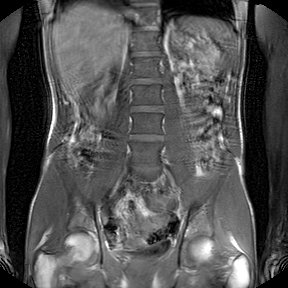

Hab mal 2 Bilder ausgesucht....einmal die Bandscheibe L5/S1. Da sieht man schon das der Kern beschädigt und nicht mehr intakt ist und das Gewebe Richtung Spinalkanal austritt. In dem Bild geht es noch. In anderen Aufnahmen ist es noch deutlicher zu sehen. Ich finde aber auch dass das alles etwas täuscht im liegenden und entspannten Zustand. Und dann das Becken bzw. an den Gelenken finde ich sieht man ganz gut den Unterschied.

H071D9FB00.jpg

H071D9FB00.jpg (20.41 KiB) 26163 mal betrachtet

H071DA0A00.jpg

H071DA0A00.jpg (46.7 KiB) 26163 mal betrachtet

Zumindestens in der LWS sehe ich bei Dir höchstens eine minimale Skoliose, die wahrscheinlich nicht behandlungsbedürftig ist. Definitiv kann Dir das nur ein auf Skoliose spezialisierter Arzt sagen. Bei Dir geht es bestimmt nicht um eine Skoliose-OP sondern "nur" um die durch den LWS Verschleiss hervorgerufene Probleme. Ein Skoliose-Korsett wirst Du bestimmt nicht brauchen. Wenn Korsett dann wird das ein reines Stützkorsett und das ist viel besser zu tragen. An Deiner Stelle würde ich bei den Ärzten eine minimalinvasive Therapie durchsetzen mit PRT-Spritzen an die schmerzenden Wirbel als Anfang.